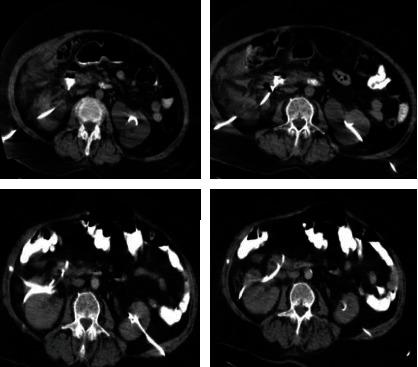

Herein, we reported a duodenal perforation case as an intestinal injury during a percutaneous nephrostomy procedure. A 73-year-old woman with bilateral nephrostomy catheters was applied to the emergency service with right flank pain. Early in the day, her bilateral nephrostomy catheters had been changed. On physical examination, she had a defense and rebound at her right quadrant, and costovertebral angle tenderness was also positive. In the contrast-enhanced abdominal computed tomography scan, the right nephrostomy catheter was located in the second part of the duodenum, and the contrast agent did not leak into the peritoneum from the injury area. We decided on conservative management of the case with active surveillance using daily blood tests and physical examinations. The nephrostomy catheter in the duodenum was left to prevent fistula between the duodenum and the skin, and a new one was placed in the right kidney. The broad spectrum antibiotherapy regime was applied, and the patient was followed up closely. The catheter in the duodenum was removed on the 20th day, uneventfully, and the patient was discharged successfully on the 24th day with her permanent bilateral nephrostomy tubes. On the first follow-up, one month later, the patient had no active medical complaint.

在此,我们报告一例经皮肾造瘘术期间十二指肠穿孔作为肠道损伤的病例。一名73岁双侧肾造瘘管的女性因右侧胁腹疼痛被送往急诊。当天早些时候,她的双侧肾造瘘管已更换。体格检查时,她右下腹有防御性反应和反跳痛,肋脊角压痛也呈阳性。在腹部增强计算机断层扫描中,右肾造瘘管位于十二指肠第二部,造影剂未从损伤部位漏入腹膜。我们决定对该病例进行保守治疗,通过每日血液检查和体格检查进行积极监测。十二指肠内的肾造瘘管予以保留以防止十二指肠与皮肤之间形成瘘管,并在右肾置入一根新的造瘘管。应用广谱抗生素治疗方案,并对患者进行密切随访。十二指肠内的导管在第20天顺利拔除,患者在第24天带着永久性双侧肾造瘘管成功出院。在1个月后的首次随访中,患者无活动性医疗主诉。